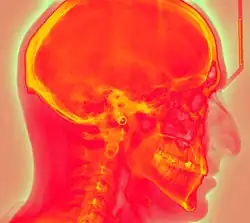

Projectional radiography using a photostimulable phosphor plate as an X-ray detector can be called "phosphor plate radiography"[1] or "computed radiography"[2] (not to be confused with computed tomography which uses computer processing to convert multiple projectional radiographies to a 3D image).

Computed radiography is used for both industrial radiography and medical projectional radiography. Image plate detectors have also been used in numerous crystallography studies.[5]

Medical X-ray Imaging

In phosphor plate radiography, the imaging plate is housed in a special cassette and placed under the body part or object to be examined and the x-ray exposure is made. The imaging plate is then run through a special laser scanner, or CR reader, that reads and converts the image to a digital radiograph. The digital image can then be viewed and enhanced using software that has functions very similar to other conventional digital image-processing software, such as contrast, brightness, filtration and zoom. CR imaging plates (IPs) can be retrofitted to existing exam rooms and used in multiple x-ray sites since IPs are processed through a CR reader (scanner) that can be shared between multiple exam rooms.[6]